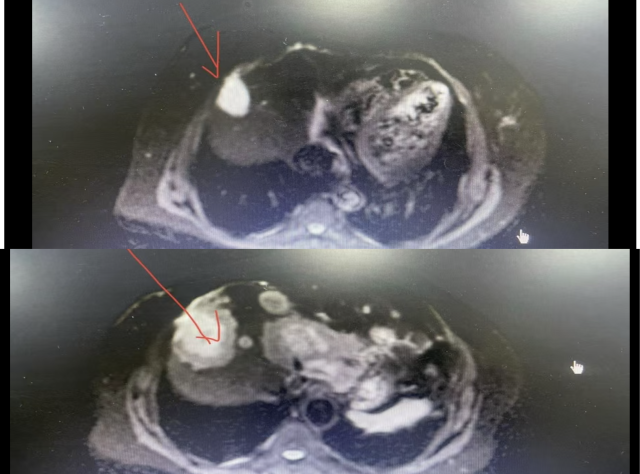

2021-08-06 乳腺增强 MRI 示:右乳占位,考虑乳腺癌,并累及右侧乳头,伴右腋下淋巴结转移;左腋下散在小淋巴结。

2021-11-08 乳腺增强 MRI 示:「右乳腺癌新辅助化疗后」复查:与 2021.8.7 日片比较,右乳肿物较前明显缩小,ADC 值较前升高,早期强化率较前较低,多点 测量时间-信号强度曲线呈缓慢上升,右腋下淋巴结转移较前减小;建议结合临床对比前片。

2021-11-08 乳腺增强 MRI 示:“右乳腺癌新辅助化疗后” 复查:与 2021.8.7 日片比较,右乳肿物较前明显缩小,ADC 值较前升高,早期强化率较前较低,多点 测量时间-信号强度曲线呈缓慢上升,右腋下淋巴结转移较前减小;建议结合临床对比前片。